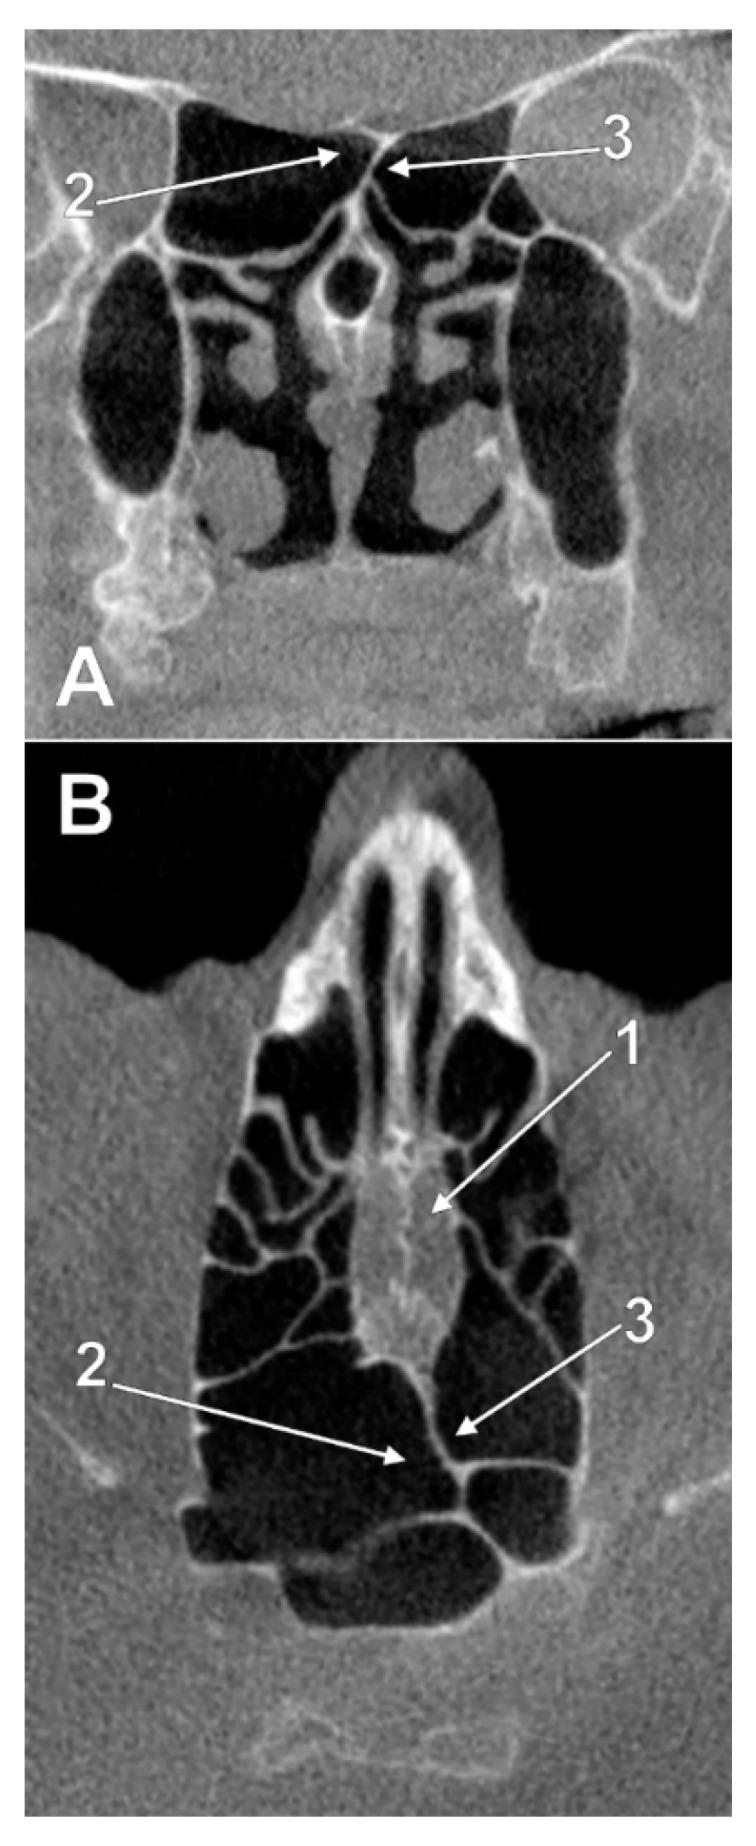

For good surgical performance, sound knowledge of anatomy is required. Although the ethmoid air cells and sphenoid sinuses are subject to a high degree of variation, their possible extensions above the nasal fossa at the posterior end of the cribriform plate of the ethmoid bone (CPEB) were seemingly overlooked. We retrospectively studied 162 case files from 55 male and 107 female cases, with ages varying from 42 to 80, which were scanned using Cone Beam Computed Tomography. In 56.17% of cases, an unpneumatized CPEB (type I) was found. Nasal roof recesses of ethmoidal origin (type II) were found at the posterior end of the CPEB in 20.37% of cases. Different types of sphenoidal pneumatizations of the posterior end of the CPEB (type III) were found in 22.83% of the cases. Onodi cells projected nasal roof recesses (type IV) in only 10 cases. In all types, nasal roof recesses were found either above the CPEB or within/underneath it. Moreover, such nasal roof recesses were found to be either unilateral, extended contralaterally, or bilateral. As such recesses of the posterior CPEB, previously overlooked, belong to the posterior rhinobase, they should be carefully documented preoperatively to avoid unwanted surgical damage to the olfactory bulb or CSF fistula.

为了获得良好的手术效果,需要对解剖学有扎实的了解。尽管筛骨气房和蝶窦的结构具有高度的可变性,但人们似乎忽略了它们在筛骨筛板后端(CPEB)鼻腔上方可能的延伸。我们回顾性地研究了 162 例 55 名男性和 107 名女性的病例文件,这些患者的年龄从 42 岁到 80 岁不等,他们均使用锥形束 CT 进行了扫描。在 56.17%的病例中,我们发现了未气化的 CPEB(I 型)。在 20.37%的病例中,我们在 CPEB 的后端发现了筛骨起源的鼻顶隐窝(II 型)。在 22.83%的病例中,我们发现了不同类型的 CPEB 后端蝶窦气化(III 型)。仅在 10 例中发现了 Onodi 细胞突出的鼻顶隐窝(IV 型)。在所有类型中,鼻顶隐窝要么位于 CPEB 上方,要么位于 CPEB 内部/下方。此外,这些鼻顶隐窝可能是单侧的、向对侧延伸的或双侧的。由于之前被忽视的 CPEB 后端的这些隐窝属于后鼻基底,因此应该在术前仔细记录,以避免对嗅球或 CSF 瘘管造成不必要的手术损伤。